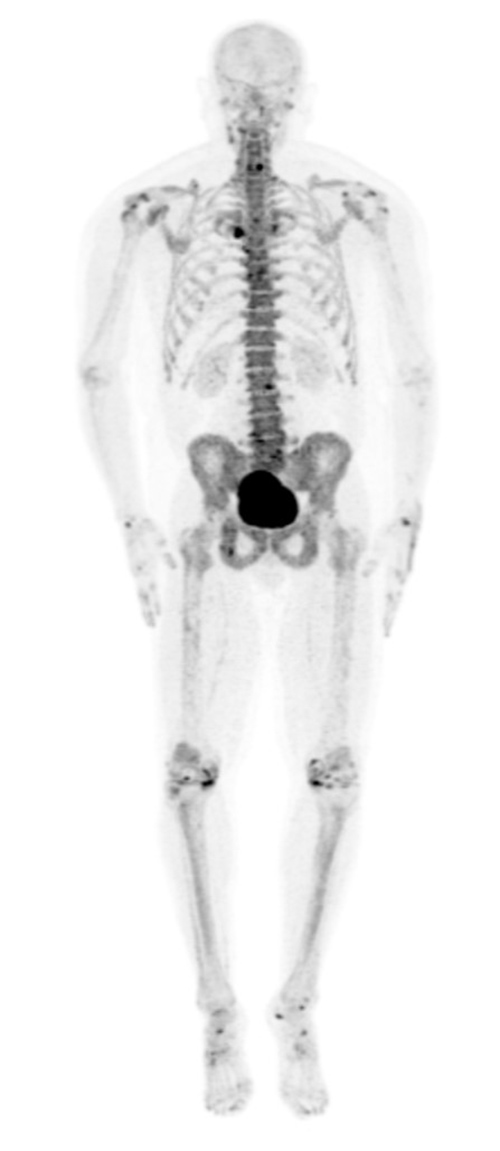

Normal whole body pediatric and adult bone scintigraphy with technetium 99m methylene diphosphonate (MDP) display different features (figure 1). In the pediatric population there is intense radiotracer uptake in the growing physes of long bones. Normal adult whole body planar bone scans with Tc-99m MDP demonstrates normal expected uptake in the bilateral sacroiliac joints, iliac crest, acromioclavicular joints, sternoclavicular joints, and nasal region. Normal radiotracer activity is excreted into the kidneys and urinary bladder.

Normal adult whole body bone scan Tc-99m MDP demonstrates normal expected uptake in the bilateral sacroiliac joints, iliac crest, acromioclavicular joints, sternoclavicular joints and nasal region. Normal radiotracer activity is excreted into the kidneys and urinary bladder. |